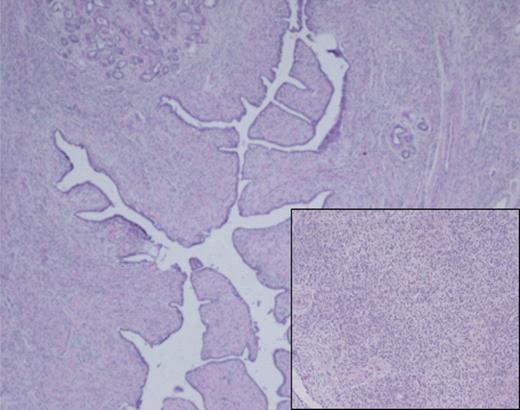

Histological analysis of the surgical specimen demonstrated a diffuse fibroepithelial lesion showing an intracanalicular growth pattern. Lobular architecture is preserved for the most part, and a variably cellular stromal component was seen throughout with focal stromal overgrowth pattern. Densely cellular spindle cell component was also noted (inset).